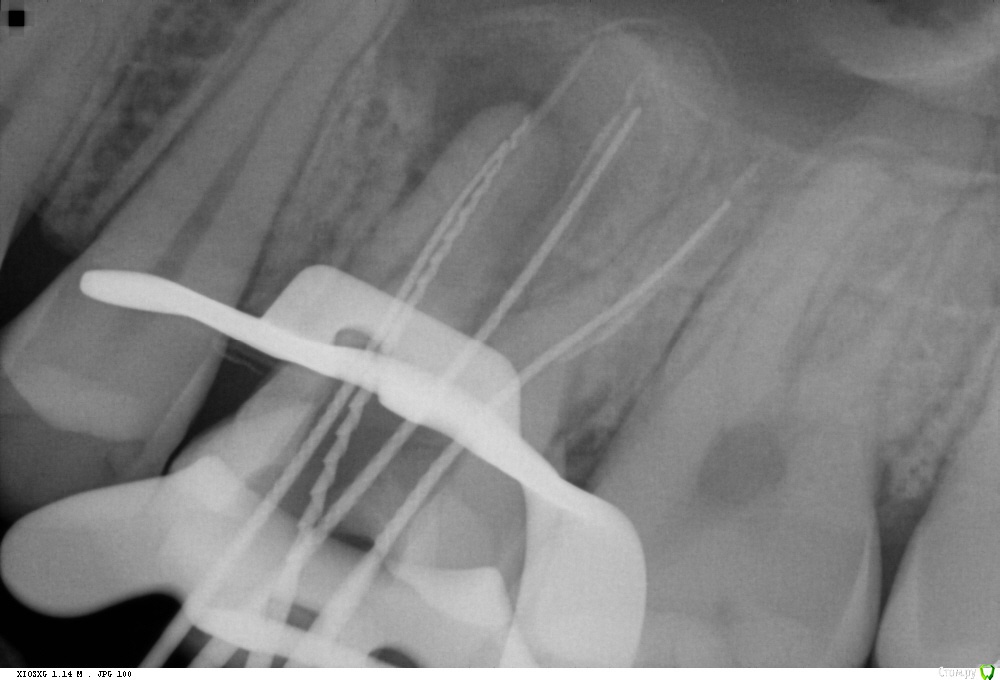

229KAMA Опубликовано 24 октября, 2016 Поделиться Опубликовано 24 октября, 2016 Пришел пац, от ортопеда, пан, или пропал, сломан в канале титановый штифт, что думаете делать?Оптики нет...Обязательно попытайтесь. Даже без увеличения шансов что сможете получить положительный результат очень велики.Вопервых по снимку отломок в ровном канале,в средней трети(даже более коронарнее),сам канал прямой есть возможность для маневра,если не ошибаюсь верхний центральный резец.Сначала пикой алмазной очень акуратно (я это делаю ультрозвуком, иногда наконечником но на малых оборотах) но и на глубину ну скажем так не более чем 0,5 -0,3мм по периметру обломка пройтись. Так чтобы отломок как пенек торчал в просвете канала. Далее эндочаком водите по этой канавке врашаясь вокруг обломка желательно врашения на отвинчивание резьбы.(если есть) если нет резь бы а просто насечки всеравно врашательные движения и иногда прямо по самому обломку секунд 5-6 постукивать. Долго , нудно , не сильно давите , мойте ,(я реже с водой просто долблю) визуальный контроль вашей уз долбежки и предположительно через час или полтора обломок может выпрыгнуть из канала.(может и намного раньше.) Если без воды уз гоняете , незабудте о том что насадка греется и необожгите пациента это так к слову , думаю все итак сами знаете.Обязательно попытайтесь. 1 Ссылка на комментарий